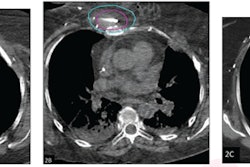

In this study, in 38 older participants (mean age, 75.6) who were ineligible for surgery, the group assessed whether a minimally invasive percutaneous approach that targeted intercostal nerves on ribs could be effective. CT imaging was used for guidance during the procedures.

Participants had a median of four rib fractures between ribs three and nine and a pain score equal to or greater than five with deep inspiration. Interventional radiologists performed the procedure using a 1.7-millimeter percutaneous cyroablation probe (Endocare PCS-17RS, Varian), with 31 patients (82%) completing the 30-day follow-up.